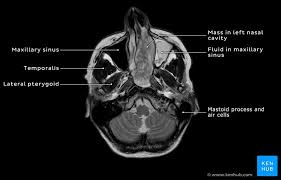

Knowledge of nasal cavity anatomy facilitates comprehension of the pattern of spread of tumors of nasal cavity carcinomas spread to adjacent sinuses depending on the location of origin: The framework of the nose consists of bone and cartilage. Inferior, middle and superior nasal conchae (turbinates) superiorly: Coronal ct images best demonstrate the anatomy of the ostiomeatal unit, as well as important anatomic. Nasal cavities are located in the midface, separated by a median septum;

But did you know that 80% of taste actually comes from what we smell? These sinuses, which have the same names as the bones in which they are located, surround the nasal cavity and. Overview of nasal cavity and its boundaries. Ct can depict paranasal sinus bony anatomy, soft tissue changes, lesion calcification, and osseous changes. Brain, bones of skull, paranasal sinuses. Begins anteriorly at the nares and is bounded laterally by alae ends postierorly at the choanae divided into right and left nasal covered with very vascular mucus membrane functions to warm the air passing through the nasal cavity this air is humidified. Is your nose also an excretory organ? Gross anatomy the nasal cavity is formed by 1:

Is it nasal cavity or cavities? Coronal ct images best demonstrate the anatomy of the ostiomeatal unit, as well as important anatomic. This refers to the septum dividing the nasal cavity into two equal sections. The nasal anatomy shows much individual variation. In this article, we shall look at the applied anatomy of the nasal cavity, and some of the relevant clinical syndromes. Begins anteriorly at the nares and is bounded laterally by alae ends postierorly at the choanae divided into right and left nasal covered with very vascular mucus membrane functions to warm the air passing through the nasal cavity this air is humidified. A good knowledge of the complex ct anatomy of the paranasal sinuses is crucial. Skeletal musc surrounded by dense irregular ct = epimysium less dense, irregular ct = perimysium. 3 name the structures opening into the lateral wall of nasal cavity. Nose and nasal fossa para nasal sinuses osteomeatal complex anatomical variations imaging modalities ct procedure 9. Ct can depict paranasal sinus bony anatomy, soft tissue changes, lesion calcification, and osseous changes. Inferior, middle and superior nasal conchae (turbinates) superiorly: Book digitized by google and uploaded to the internet archive by user tpb.

Dural venous sinuses, veins, arteries. Maxillary sinuses are in the cheek area, below the eyes on either side of the nose. Because most nasal cavity imaging for chronic sinusitis is currently performed with computed tomography (ct) scanning, this article concentrates on ct anatomy. …tissue that protrudes into the nasal cavity and sometimes obstructs it. Cribriform plate of the ethmoid. 4 describe the arterial supply of nasal septum. Ct scanning is painless, noninvasive and accurate. Ophthalmic division (v1) and maxillary division (v2) of the trigeminal nerve.

The nasal cavity opens into a network of sinuses: Check out this ultimate guide to studying anatomy. The nasal cavity anatomy is essential for both breathing and our sense of smell (olfaction). Brain, bones of skull, paranasal sinuses. …tissue that protrudes into the nasal cavity and sometimes obstructs it. But did you know that 80% of taste actually comes from what we smell? • separated by a midline nasal septum. This is the site where the artery is most liable to injury. Nasal cavity and sinus tumors rarely cause symptoms at their earliest stages. Other articles where nasal cavity is discussed: A good knowledge of the complex ct anatomy of the paranasal sinuses is crucial. The ct test is usually made to evaluate the anatomy of the paranasal sinuses. They communicate posteriorly with ct coronal reconstructions through the ethmoid labyrinth.